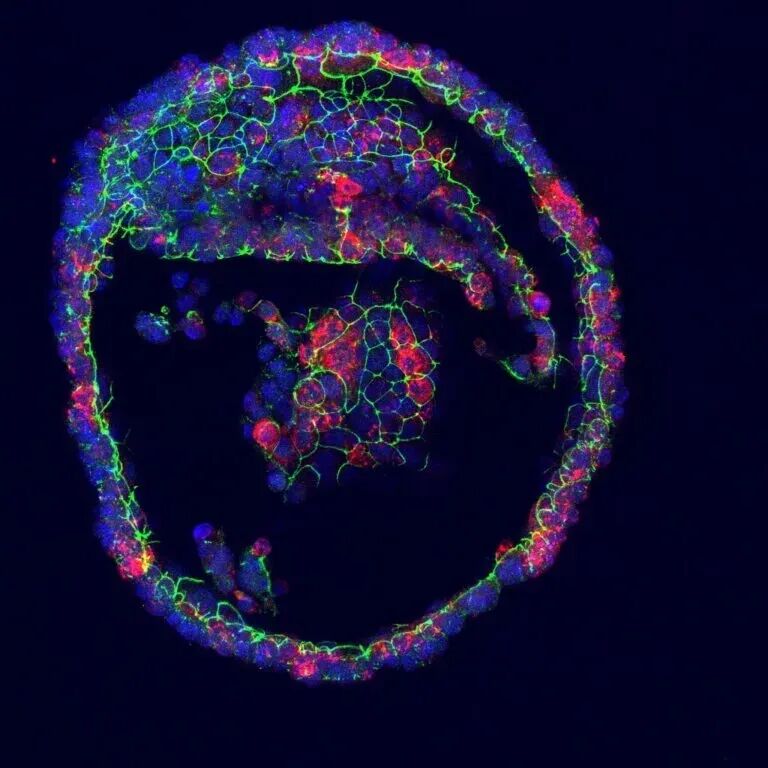

因此,泪腺分泌的泪液十分重要。科学家们取得了一项重要的突破:利用人类干细胞,他们在培养皿中培育出了人类泪腺模型,并首次成功地让这团细胞流出了眼泪。

▲蓝色是细胞核,红色标记的是产生的眼泪成分